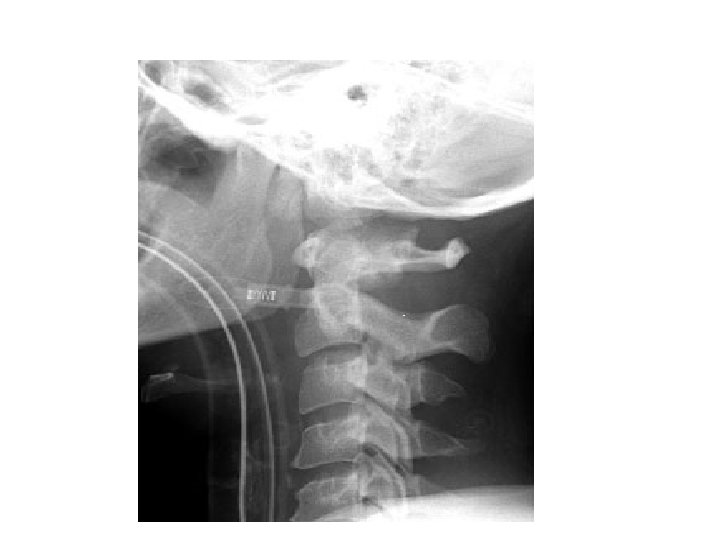

HANGMAN’S FRACTURE • • Fractures through pars interaticularis of the axis Unstable if occurs with facet dislocation Mechanism – hyperextension Features – – Prevertebral soft tissue swelling – Avulsion of anterior inferior corner of C 2 assoc. with rupture of the ant. Longitudinal ligament – Anterior dislocation of C 2 body – Bilateral C 2 pedicle fractures.